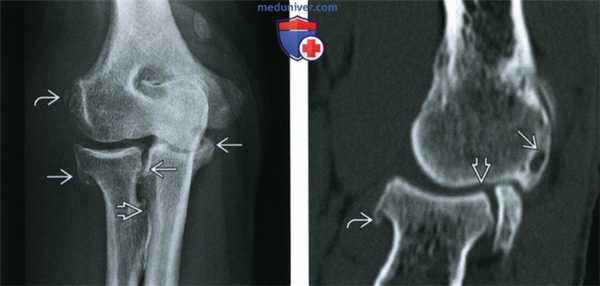

(Слева) Рентгенография в ПЗ проекции: признаки умеренно выраженного ОА локтевого сустава, включая остеофиты и гипертрофию костной ткани в области бугристости лучевой кости. Оссификат, покрытый кортикальным слоем в проксимальном сухожилии разгибателя, соотносится с хронической тендинопатией, либо предшествующим повреждением.

(Справа) КТ, сагиттальная проекция, без контрастного усиления: хронический ОА локтевого сустава с субхондральными кистами, остеофитами и сужением суставного пространства. Распространение костных патологических изменений иногда лучше визуализируется при КТ, чем при рентгенографии.